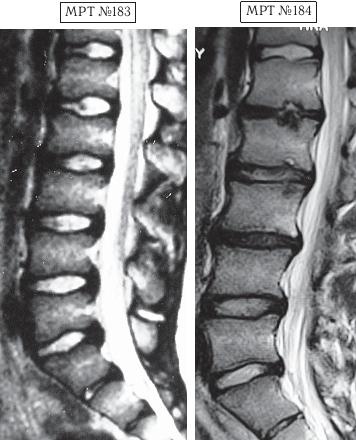

На МРТ №«176 — состояние поясничного отдела позвоночника после двух недель лечения методом вертеброревитологии. Наблюдается уменьшение грыжи межпозвонкового диска в сегменте LV—SI. ![]() На МРТ № 177 (увеличенный фрагмент МРТ № 175) наблюдается грыжа межпозвонкового диска сегменте LV—SI. На МРТ № 178 (увеличенный фрагмент МРТ № 176) состояние межпозвонкового диска после двух недель лечения методом вертеброревитологии: уменьшение грыжи межпозвонкового диска в сегменте LV—SI. Многие пациенты спрашивают меня после лечения: «Куда уходят грыжи?» Этот вопрос задаётся столь часто, что уже просто родилась ответная дежурная фраза: «Откуда пришли, туда и ушли — домой, назад в межпозвонковый диск». Конечно, это шутка, но, как известно, в каждой шутке есть доля шутки. Естественно, процессу ретрузии секвестра грыжи межпозвонкового диска способствуют создание искусственных оптимальных условий, правильное физиологическое построение биомеханической конструкции, благодаря методу вертеброревитологии. Данная конструкция держится, по моим наблюдениям, достаточно долго, при условии, что человек соблюдает соответствующие элементарные рекомендации. В общем-то, должен заметить, что в последнее время эпизодов, связанных с последствиями укрепления мышечного корсета, стало значительно больше. Наверное сказывается действие профессиональной рекламы на непрофессиональное восприятие общественности. В качестве примера приведу для сравнения два случая из моей практики — истории людей, которые между собой незнакомы. Эти случаи объединяют возраст пациентов (четырнадцать лет), схожесть причин, вызвавших остеохондроз поясничного отдела позвоночника (чрезмерное увлечение компьютером) и первые шаги в лечении патологии. У первого пациента боли в поясничном отделе позвоночника появились в возрасте тринадцати лет, у второго — в двенадцать. Обоих родители водили в больницу, где им назначалось практически идентичное лечение: медикаментозная терапия, массаж, ЛФК и физиотерапия. Как всегда бывает в таких случаях из прописанного лечения пациентами что-то выполнялось, что-то нет. Но в конечном итоге, оба оказались на приёме у мануальных терапевтов. В первом случае у пациента, спустя определённое время, случилось сильное обострение. Сделали МРТ № 179, диагностировали секвестрированную грыжу межпозвонкового диска. Родители первого парня привели его на лечение ко мне в клинику. Так случилось, что в тот же день за консультацией обратились родители второго парня вместе с ним. Они также принесли снимки (МРТ № 183). У второго парня наблюдалась начальная стадия развития остеохондроза. В принципе ничего сложного, можно было подкорректировать, восстановить здоровье и этого юного пациента. Однако случилось так, что родители первого парня, в отличие от родителей второго, остановили свой выбор на клинике вертеброревитологии. Их сын прошёл курсы лечения данным методом и теперь за здоровье парня можно только порадоваться.

На МРТ № 179 наблюдается состояние поясничного отдела позвоночника (до лечения): сглаженность поясничного лордоза, протрузия (компенсированная спондилёзом) в сегменте LIV—LV, секвестрированная грыжа межпозвонкового диска в сегменте LV—SI, абсолютный стеноз позвоночного канала. На МРТ № 180 — состояние поясничного отдела позвоночника после лечения методом вертеброревитологии: естественный физиологический лордоз поясничного отдела позвоночника, отсутствие секвестрированной грыжи межпозвонкового диска в сегменте LV—SI, отсутствие стеноза. Но самое интересное можно рассмотреть на МРТ № 181 и МРТ № 182. ![]() На увеличенных фрагментах вышеприведенных снимков наблюдается состояние сегмента LV—SI до лечения (МРТ № 181) и после лечения методом вертеброревитологии (МРТ № 182). На МРТ № 182 чётко прослеживается не только отсутствие секвестрированной грыжи межпозвонкового диска в сегменте LV—SI но и активный процесс восстановления межпозвонковых дисков (репаративная регенерация) в сегментах LIV—LV, LV—SI, и главное — процесс восстановления их пульпозных ядер. Так что можно образно сказать, что данный парень вытянул в жизни, не без помощи своих родителей, счастливый билет: он уже практически здоров, грыжа диска устранена без операции и биомеханика позвоночника восстановлена, а для молодого организма это немаловажный фактор. Но главное, он получил бесценный, собственный опыт того, что компьютер компьютером, а собственное здоровье ценнее всего и его надо беречь смолоду. А вот второго парня вместе с его родителями я увидел только через полтора года после нашей первой встречи, когда они вновь пришли ко мне на консультацию в клинику. На этот раз состояние его позвоночника было удручающим. Оказывается, по инициативе родителей их семья посетила широко рекламируемую частную клинику, которая специализируется на кинезитерапии — лечение движением заболеваний позвоночника. Там с ними обстоятельно побеседовали по поводу того, как «активная кинезитерапия оказывает саногенетическое действие, устраняя патобиомеханический субстрат синдрома», что для людей, неискушённых в медицинских терминах, равносильно пафосной речи из советской комедии «Операция «Ы» и другие приключения Шурика»: «В то время, когда наши корабли бороздят просторы Вселенной…». А потом, чтобы пациент-клиент ничего не перепутал, выдали специальную брошюрку, где были подробно расписаны советы вместе с физическими упражнениями, направленными на укрепление мышц спины, которые по рекомендации врачей данной клиники необходимо было выполнять для «лечения» остеохондроза. К сожалению, на тот момент родители этого юноши не были осведомлены о негативном влиянии подобных упражнений, направленных на укрепление мышечного корсета, на позвоночник, поражённый дегенеративно-дистрофическим процессом. А когда случилась беда и пошли необратимые процессы, было уже поздно что-либо предпринимать. Вот уж правду в народе говорят: «Здоровье не купишь — его разум дарит».